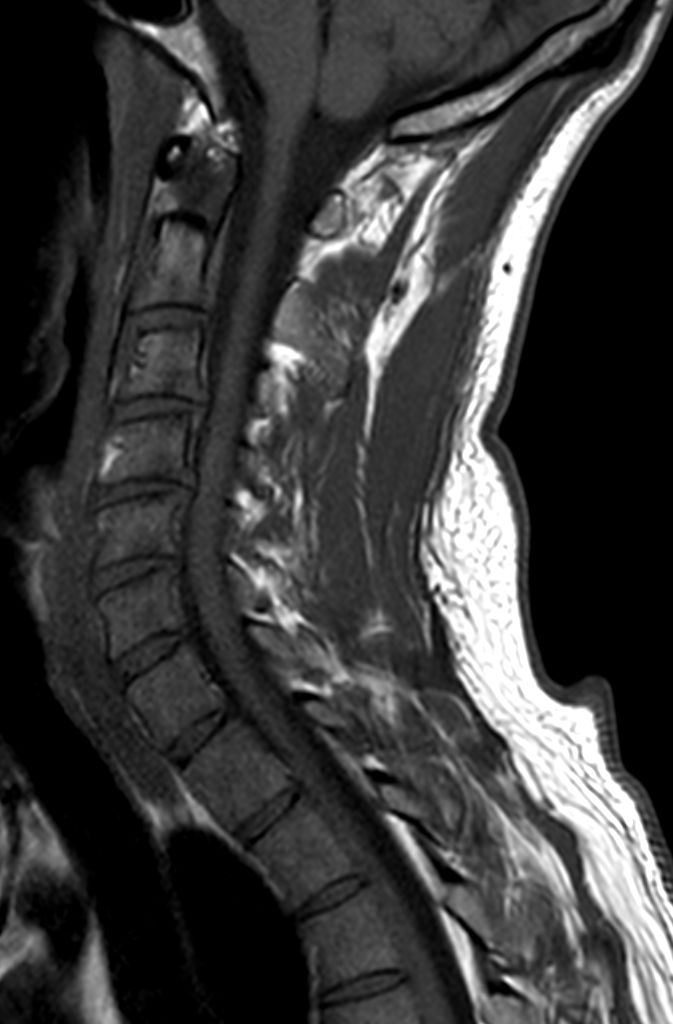

T2w TSE mDIXON XD (In Phase)